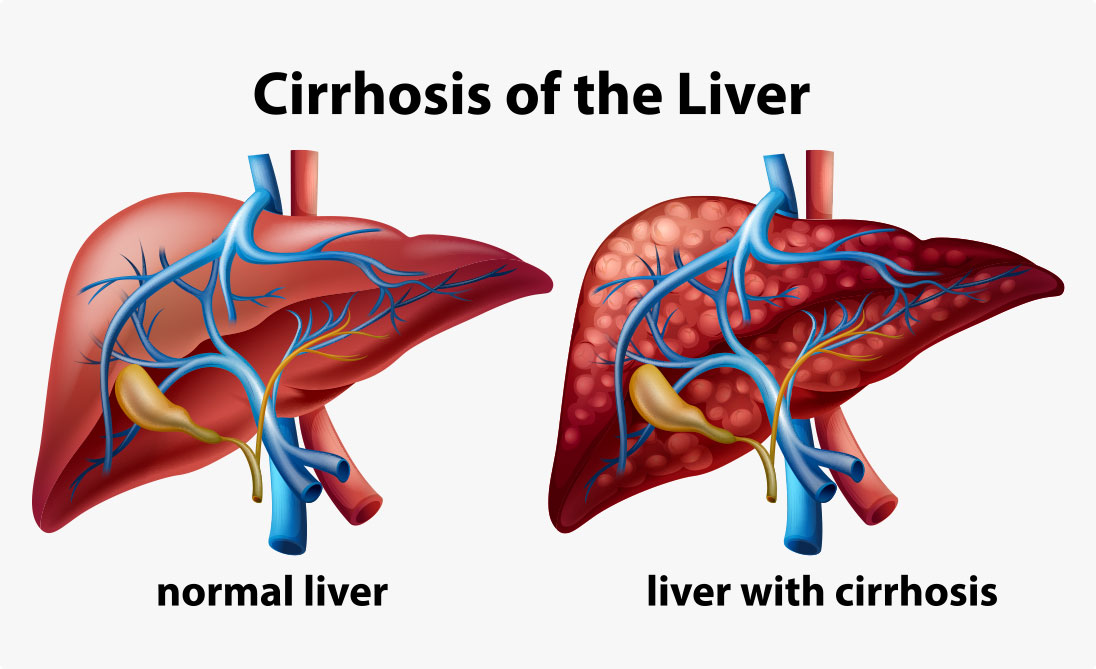

Liver Cirrhosis

Liver cirrhosis occurs when healthy liver cells are replaced with scar tissue, preventing the liver from functioning properly. These scar tissues are formed as a result of long-term damage to the liver – excessive alcohol abuse, hepatitis B and C infection, or fatty liver from diabetes and obesity.

If a patient has cirrhosis, it means that their liver has reached the stage where it can no longer regenerate.